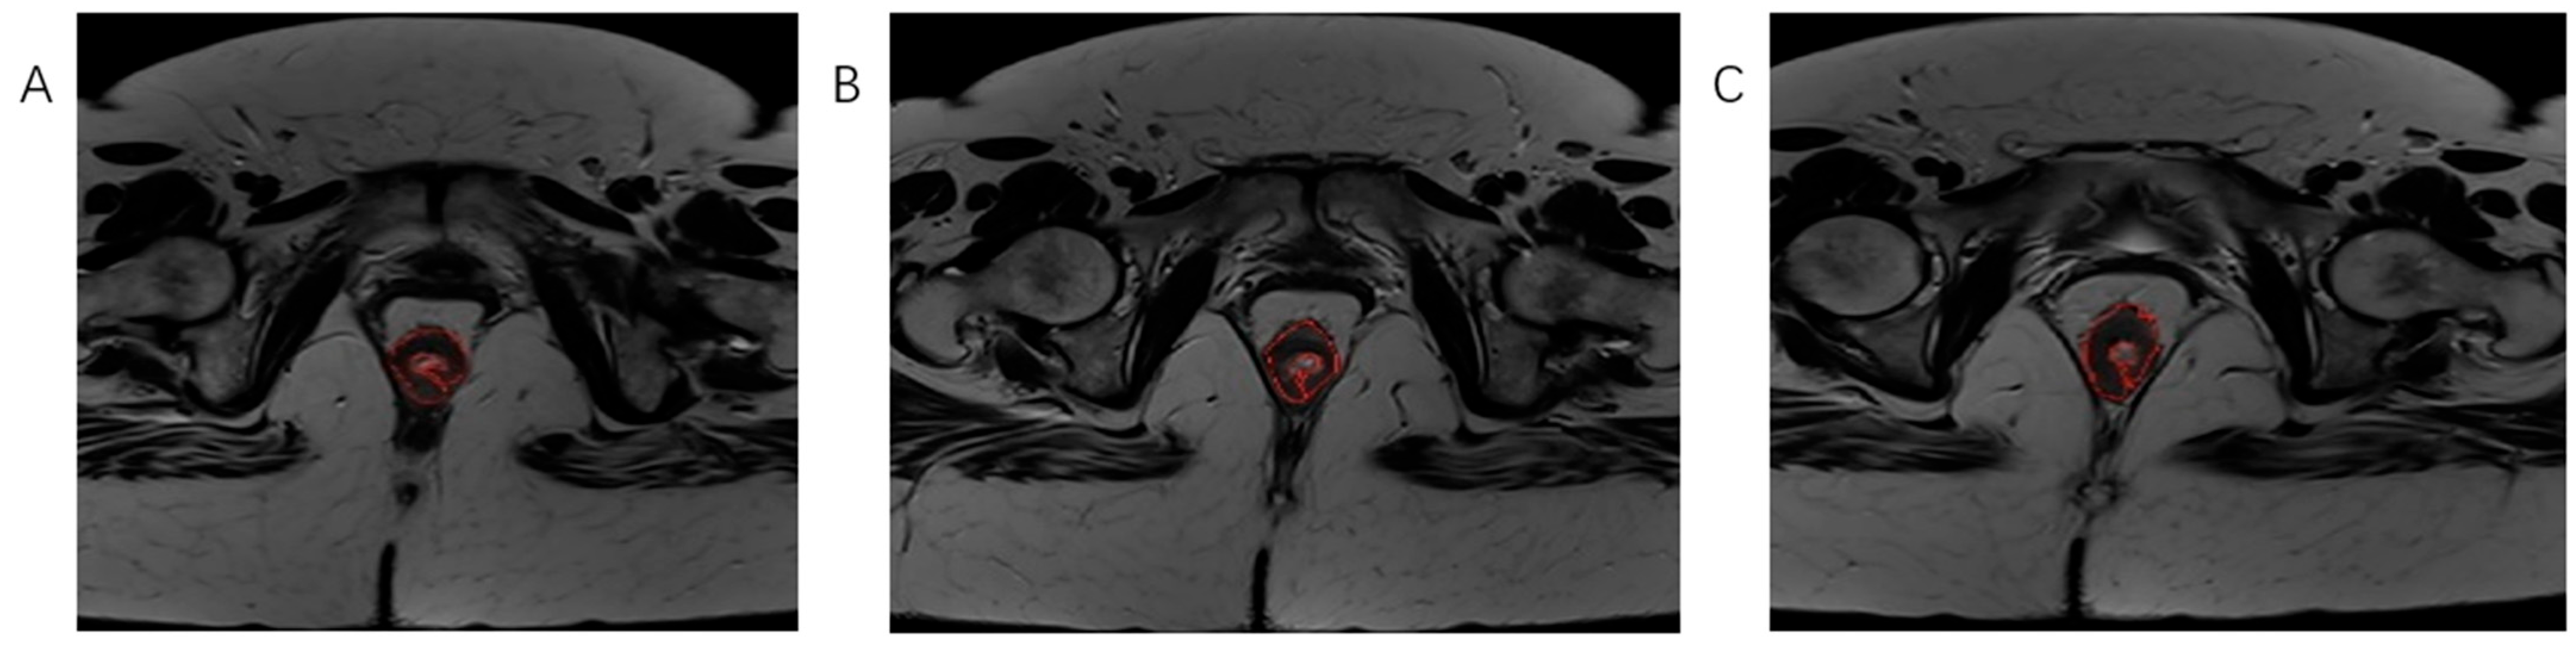

Using software MIPAV (Medical Image Processing, Analysis, and Visualization) version 11.3.2, developed by the National Institutes of Health, Bethesda, MD, USA, histogram analysis was performed on both MRI examinations. All tumor segmentations were performed by a board-certified GI radiologist with 8 years of experience in rectal cancer imaging, blinded to pathological results. Segmentation was performed on T2-weighted axial sequences with regions of interest manually drawn on each slice containing visible tumor while carefully excluding surrounding fat, mesorectal fascia, and bowel lumen. It is followed by volume of interest (VOI) creation and automatically histogram parameter calculation (Figure 3, Figure 4 and Figure 5). The following 7 histogram parameters were measured: mean (average pixel intensity value in the region), standard deviation (measure of pixel intensity variation), median (middle pixel intensity value), kurtosis (measure of distribution “peakedness”), skewness (measure of pixel distribution asymmetry), and 5th and 95th percentiles (markers of distribution extremes). Other than the above-mentioned, other measured morphological, functional, and volumetric parameters are beyond the scope of this study.

Figure 3.

The process of tumor tissue segmentation by manually outlining the ROI on successive slices of T2-weighted axial sequences on MRI examination (A–C).

Figure 4.

Marking (A) and calculating (B,C) histogram parameters were shown on the initial, pre-treatment MRI scan, T2-weighted axial sequence.